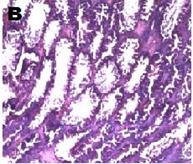

Histoarchitecture of the testes of treated animals showed mild to moderate atrophy and altered spermatogenesis (fig. 5). These were characterized by a reduction in the size of the seminiferous tubules and a decreased number of interstitial cells accompanied by spermatogenic arrest at high doses of the extract (fig. 5). The observations were in agreement with the reduced sperm numbers recorded.

Fig. 5: Photomicrograph (x40) showing histopathological profile of the testes of rat after 14 d treatment with varying doses of Carica papaya. A, B, C, D, E are control 10, 100, 300, 500 mg/kg of aqueous leaf extract of C. papaya respectively